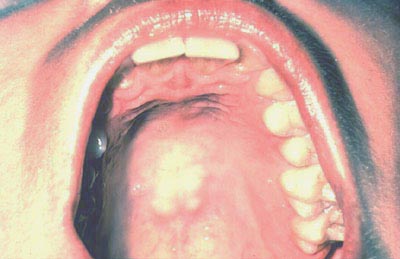

Con la boca totalmente abierta y la cabeza del paciente echada hacia atrás, presione suavemente la base de la lengua con un espejo dental. Primero inspeccione el paladar duro y luego el paladar blando.

Examine el paladar blando, úvula, trígono retromolar y los pilares anteriores..